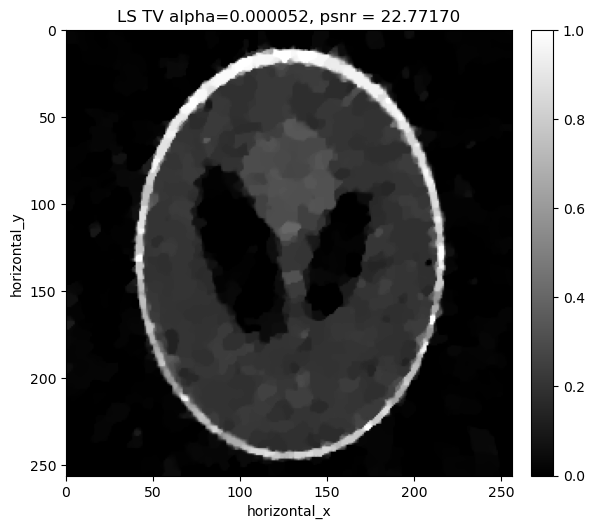

Reconstructing the noisy data using least squares with Total Variation regualrisation#

Similar to the least squares cas, in addition to the weighted least square term, we considered a Total Variation Regulariser. We minimize:

\[||Y-Ax||_{W}^{2} + \alpha \, TV(x)\]

where \(\alpha\) is the regularization parameter that balances the two terms. Again we search a range of values of \(\alpha\) to find the best one for the data.

alpha=0.000031, psnr= 21.991

alpha=0.000033, psnr= 22.275

alpha=0.000035, psnr= 22.479

alpha=0.000037, psnr= 22.621

alpha=0.000039, psnr= 22.711